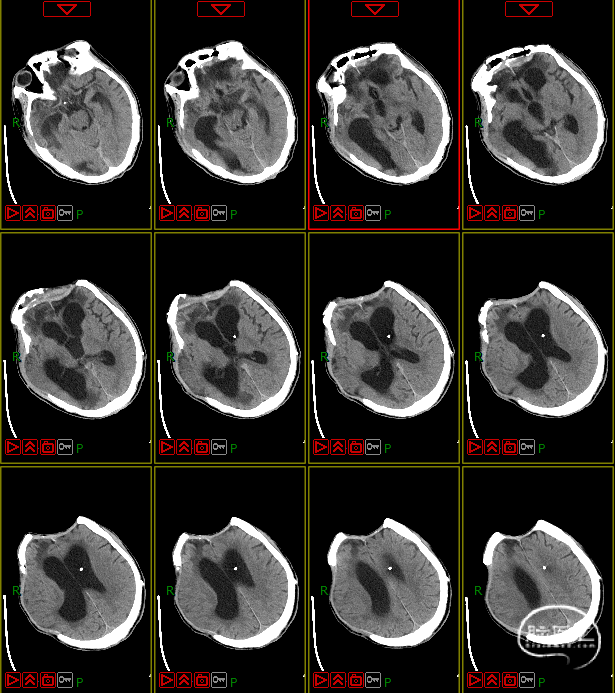

病史及症状描述:主诉:重型颅脑外伤术后意识障碍50天(7月30日入院);现病史:患者2023年6月11日因高处坠落伤在外地行开颅手术等治疗,病情平稳后带气管套管转回湘潭市中心医院(后续简称“我院”)治疗。

入院查体:GCS=E2VTM2=4T分,右侧瞳孔直径约4mm,对光反射迟钝,左侧瞳孔约3mm,对光放射灵敏,四肢关节被动屈伸活动无受限,四肢肌张力偏高,肌力查体无法配合,病理征未引出。

入院诊断:1. 右侧额颞部硬膜下血肿清除术后;2. 颅骨后天性缺损;3. 脑内多发软化灶形成;4. 脑积水;5. 左额骨凹陷性骨折;6. 颅底骨折;7. 左股骨干骨折内固定术后;8. 坠积性肺炎、胸腔积液;9. 气管切开术后;10. 右眼挫伤;11. 下肢肌间静脉血栓;12. 低蛋白血症。

4. 动态复查头部CT

8月21日复查CT:硬膜下积液增加,脑室扩张明显,间质性水肿加重;对患者治疗方案进行调整,转神经外科治疗。